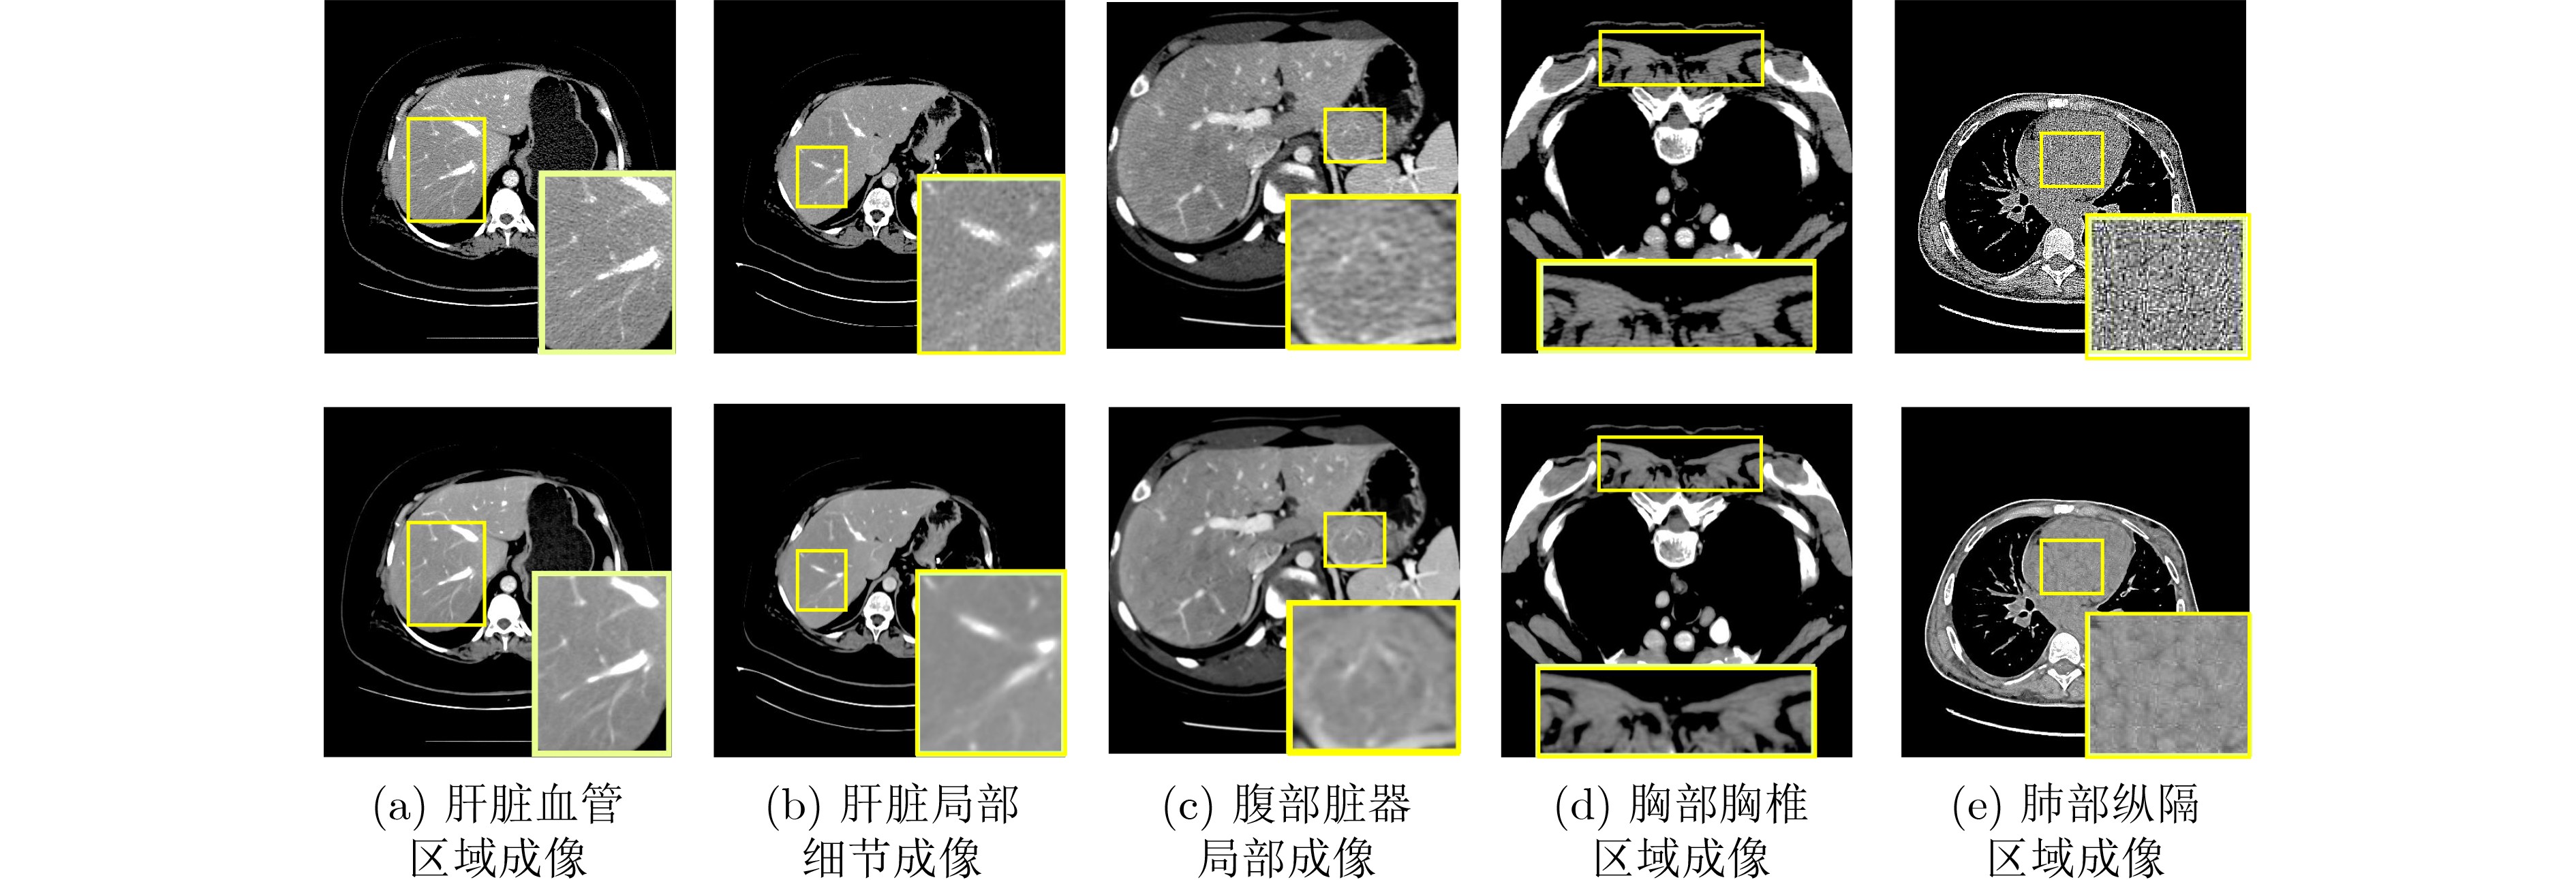

面向稀疏辐射观测的无监督三维医学图像分割方法

俞晓帆, 邹兰兰, 顾文琦, 蔡君, 康彬, 丁康

2026, 48(3): 947-959. doi: 10.11999/JEIT250841

摘要:

神经衰减场是一种具有前景的三维医学图像重建方法,此方法利用稀疏辐射测量实现与完整观察相接近的重构精度。该文提出一种无监督三维医学影像分割方法,将无监督分割与神经衰减场集成为一个端到端的网络架构。具体而言,所提网络架构包括两个阶段:稀疏测量重建和交互式三维图像分割。两个阶段可通过联合学习自适应实现互惠优化。为解决类似肛肠等复杂病灶中边界模糊和区域过度扩展的难题,所提三维分割网络的交互式三维分割阶段设计了密度引导模块,有效利用衰减系数的先验知识,调节密度感知的注意力机制,提升三维分割泛化性能。通过与南京市中医院合作构建的结直肠癌数据集以及两个公开数据集上的大量实验证明所提方法的优越性,例如与基于全辐射观测的SAM-MED3D算法相比,所提网络仅使用14%稀疏观测值,在3个数据集的平均Dice系数提升 2.0%。